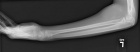

15 year old boy with left elbow mass for five years that has increased in size over the last few months as well as becoming more painful